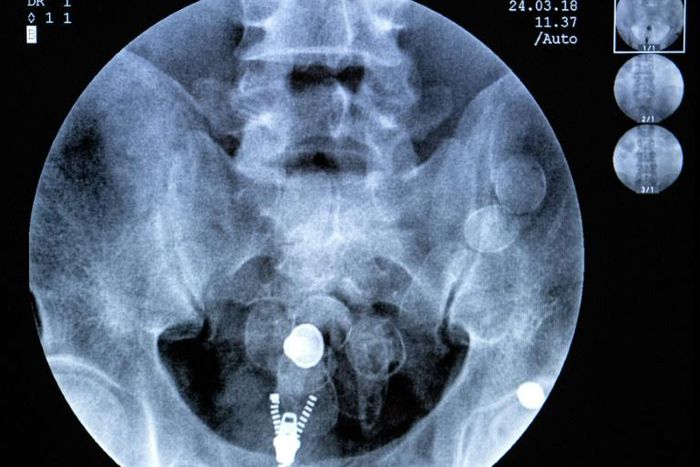

After three days and with the help of a pink laxative gel, 26-year-old Sylvain has expelled all 49 cocaine pellets he had in his body, crouched over a toilet bowl with no flush mechanism.

Long gone are the days of swallowing cocaine stuffed into condoms -- today's smugglers have gone high-tech. All the Guiana pods are the same: small, black, heat-sealed capsules about three centimetres (1.2 inches) wide.

He was arrested with two kilos of cocaine hidden in his underwear, his shoes, his suitcase and his stomach, which contained 76 pods.